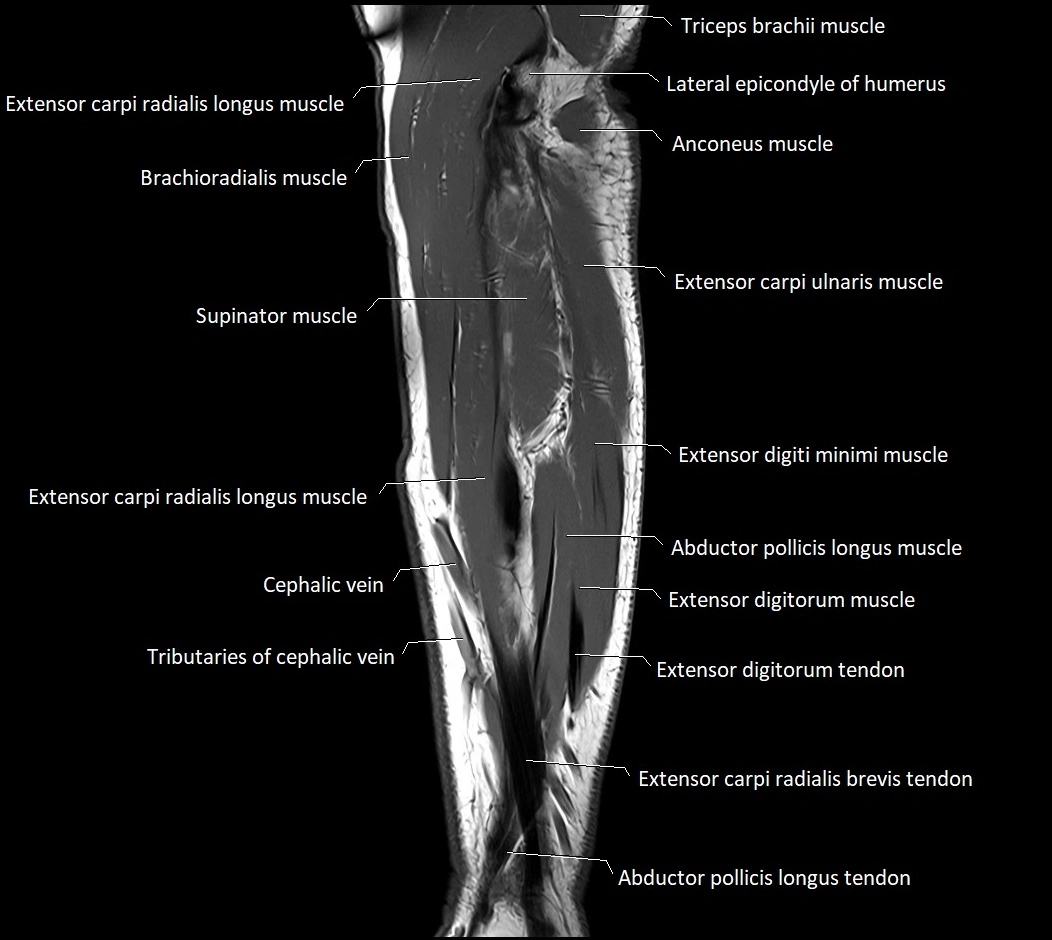

MRI images

image